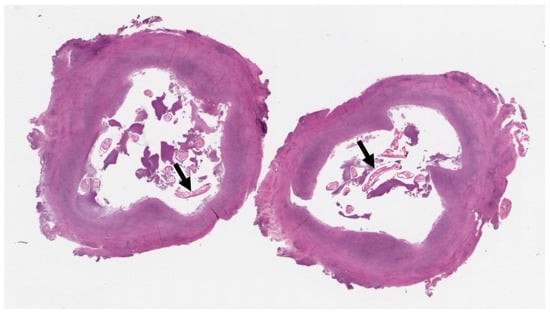

The differential diagnosis at this stage included torsion or detachment of the appendix testis (hydatid of Morgagni) versus a granulomatous infection or neoplasm. Given the uncertainty and persistence of the mass, an exploratory surgical intervention was performed. The pediatric surgeons excised an encapsulated, tough mass from the left spermatic cord (Figure 3). The mass was not adherent to the testis or epididymis. Histopathological analysis of the nodule revealed a pseudocyst with chronic granulomatous inflammation, containing fragments of helminth, surrounded by fibrinous and purulent exudate (Figure 4).

Figure 4.

Histological section of a whitish centimetric nodule: Pseudocyst with chronic granulomatous inflammation; in the lumen, fragments of helminth (black arrows) and fibrino-purulent exudate.

Definitive diagnosis of dirofilariasis is typically achieved through surgical excision and histopathological examination of the nodule [1,4]. The pathognomonic histological finding is the presence of the parasite’s thick, multi-layered cuticle [19]. While PCR has been a valuable diagnostic tool since the 1990s [20], some authors have reported discrepancies with histopathology, underscoring the importance of interpreting molecular results in conjunction with clinical and pathological findings [21,22]. In our case, non-specific histology showing helminth fragments prompted the use of PCR, which detected D. repens DNA.